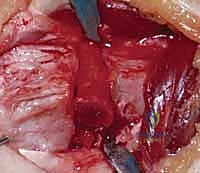

2. الشق الجراحي والوصول للعظم (Surgical Approach)

يقوم الدكتور هطيف بعمل شق جراحي دقيق (غالباً من الجهة الأمامية للرسغ - Volar Approach). يتم إبعاد الأوتار والأعصاب (مثل العصب الأوسط) والأوعية الدموية بمنتهى الحذر باستخدام تقنيات الجراحة المجهرية لحمايتها من أي ضرر.

3. قص العظم التصحيحي (The Osteotomy)

بناءً على التخطيط الثلاثي الأبعاد المسبق، يستخدم الدكتور هطيف مناشير عظمية دقيقة جداً لعمل شق في العظم في نقطة التشوه الأصلية. يتم فتح العظم وتعديل زاويته واستعادة طوله الطبيعي.